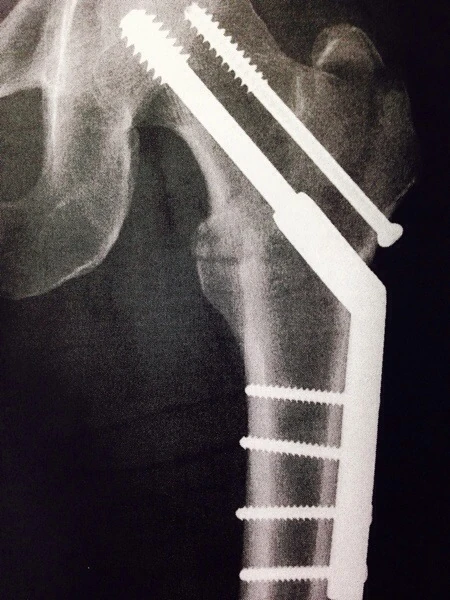

So, Dr. Karam showed me my x-ray and said that everything was good. That the bone was healing properly, etc. I really didn’t have much to ask him. I told him I’d ridden outside twice, 15 miles the day before, and he seems surprised. He said that it was fine, but I shouldn’t fall. I told him I was having a fair amount of pain in other parts of my leg. The IT band, above my knee, lower calf. He said it was from attrification and lack of use, which makes total sense.

I’ll post a couple more photos of the x-ray, etc., when I get back to Trudi’s mom’s house.

It doesn’t look so healed when I see it here.